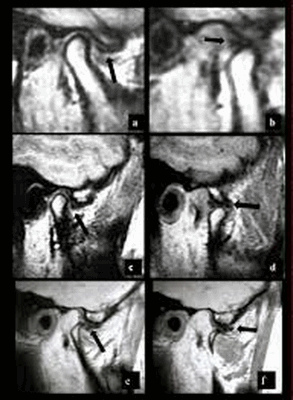

Смещения диска.

Выделяют переднее, передне-латеральное, передне-медиальное, латеральное, медиальное и заднее смещения; наиболее часто диагностируется переднее смещение диска.

Вывихи диска - фиксированный и перемежающийся (подвывих).

При фиксированном вывихе диск смещен кпереди от мыщелка и в положении открытого и при закрытом рте; при перемежающемся вывихе (подвывихе) диск смещен кпереди только при закрытом рте. При открывании рта диск возвращается в нормальное положение интерпозиции между мыщелком и суставным бугорком. При этом слышен характерный щелчок.

Перемежающийся (вправляемый) вывих /подвывих.

А. Закрытый рот. Переднее смещение диска.

Б. Рот открыт. Диск вернулся в нормальное положение между мыщелком и височной костью.

Фиксированный (невправляемый) вывих.

А. Рот закрыт. Переднее смещение диска.

Б. Рот открыт. Диск продолжает оставаться смещенным.

«Застрявший» диск.

«Застрявший» диск. PD sag изображения с открытым (А) и закрытым (Б) ртом - задний край диска (стрелка) остается в нижнечелюстной ямке височной кости. По этой причине открывание рта сильно ограничено. Вероятная причина - образование спаек.

Заднее смещение диска.

Заднее смещение диска (составляет менее 0,01% всех патологий ВНЧС).

А. Положение с закрытым ртом. Суставной диск сместился дорзально.

Б.Положение с открытым ртом. Возвращение суставного диска на уровень мыщелка нижней челюсти. Движения челюсти очень ограничены в данном случае.

Магнитно-резонансная томография ВНЧС - невправляемый вывих. Стрелкой указано хрящевое образование, которое остается смещенным при закрытом (a) и открытом (b) рте.

На МРТ ВНЧС “застрявший диск” (a - открытый рот, b - закрытый). Стрелкой обозначена задняя поверхность хрящевого образования, которая вне зависимости от движений остается в нижнечелюстной ямке.

Примером еще одной патологии, которую помогают установить функциональные пробы, является фиксированный, перемежающийся вывих и подвывих. Специалист увидит на изображении с закрытым ртом смещение внутрисуставного образования, а в открытом состоянии оно вернется на место. Описанный результат будет свидетельствовать о перемежающемся вывихе челюстного сочленения.

МР-изображение ВНЧС. a, c, e - в открытом положении, b, d, f - в закрытом. Стрелками показано переднее смещение диска с редукцией (a,b,c,d), без редукции (e,f). Выявлен остеофит на мыщелке (e,f).